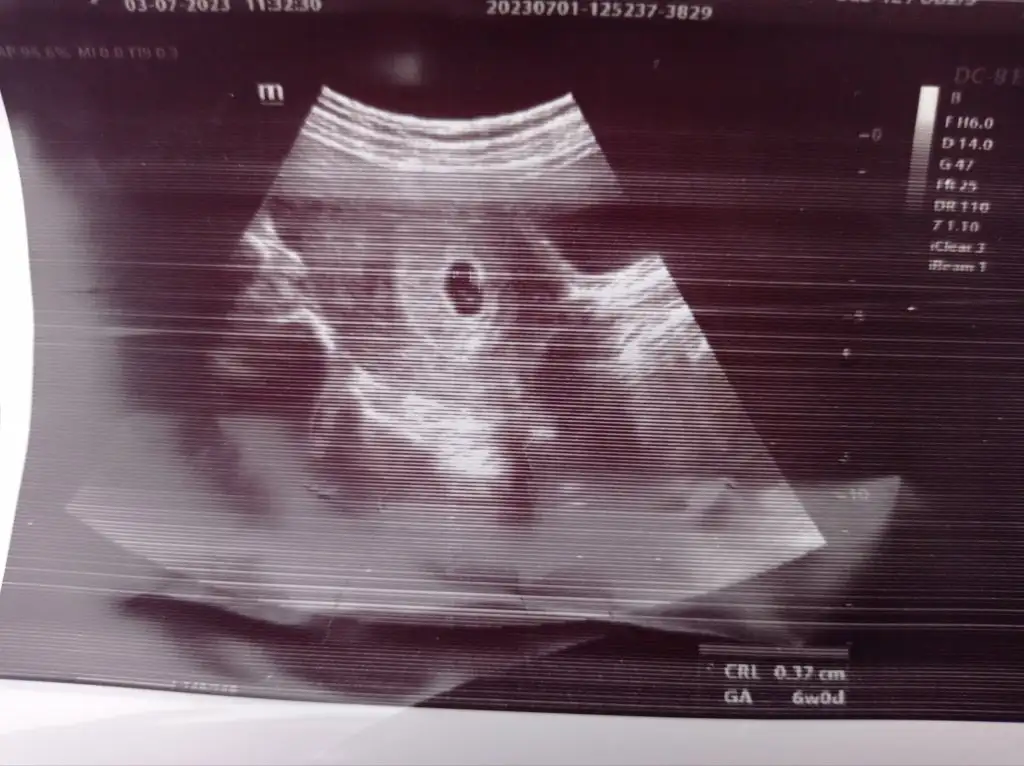

Kızlar bir tanıdığınız varsa veya doktorunuza sorabilir misiniz lütfen yardım edin. Bebeğimin katili olmak istemiyorumKızlar benim bir defa çok az parlak kırmızı kanamam gelmişti. Onunla acile gittim o gece ne kanama ne pembelik oldu bir daha. Sabahına uyuşmazlık iğnesi vurdular,beta 4300 çıktı gece sabah 4030 çıktı. Sabah doktor geldi baktı dedi ki kalp atışı ritmik, şu an iyi, kanama alanı yok. 3 saat sonra başka doktora gittim bebeğin yolk kesesi büyük normal kesesine göre, betan da aşırı düşük. Yüzde 99 düşer dedi ama benim dünden beri minicik çok çok açık pembe akıntıdan başka bir kanamam yine olmadı. Şu an uyandim yine kanamam yok. Böyle kanamasiz, ağrısız düşük olur mu. Biri öyle biri böyle dedi. Biri progestan kullan dedi. Diğeri de sadece düşüğü ertelersin dedi. Şu anda da 3. Doktor seçeneğim yok. Düşük riski varsa şehir değiştirmek de istemiyorum. Son görsel ilk doktorun sağlıklı diyen. Sonradan haftasını tekrar ölçtü 6+1 demişti Eki Görüntüle 3267882 Eki Görüntüle 3267886

Ben çok bilgili değilim bu konuda canım. Gebeliğimin ilk aylarında bende ufak bir kanama yaşamıştım doktorumu aradım hemen, o da sağlıklı bebek tutunur sağlıksız bebek tutunmaz vücut atar dedi. Bu söz çok canımı yaktı nolur tutunsun diye çok dua ettim her haliyle kabulüm dedim. Düşük riskim olmadı ama 37.haftada aniden kaybettim. Yaşadığım acı kaybetme korkusunun bin katıydı belki. Demek ki hata ettim en başta. Şimdi düşünüyorum rabbim veriyorsa da alıyorsa da vardır bir bildiği. Bebeğin sağlıklı ise ki İnşAllah sağlıklıdır senle kalır değilse annesinin vücudunu temizleyerek yeni gebeliğe daha sağlıklı hale getirerek cennette beklemeye gider. Yaşadığın bu belirsizlikte İnşAllah en kısa sürede netliğe kavuşurKızlar benim bir defa çok az parlak kırmızı kanamam gelmişti. Onunla acile gittim o gece ne kanama ne pembelik oldu bir daha. Sabahına uyuşmazlık iğnesi vurdular,beta 4300 çıktı gece sabah 4030 çıktı. Sabah doktor geldi baktı dedi ki kalp atışı ritmik, şu an iyi, kanama alanı yok. 3 saat sonra başka doktora gittim bebeğin yolk kesesi büyük normal kesesine göre, betan da aşırı düşük. Yüzde 99 düşer dedi ama benim dünden beri minicik çok çok açık pembe akıntıdan başka bir kanamam yine olmadı. Şu an uyandim yine kanamam yok. Böyle kanamasiz, ağrısız düşük olur mu. Biri öyle biri böyle dedi. Biri progestan kullan dedi. Diğeri de sadece düşüğü ertelersin dedi. Şu anda da 3. Doktor seçeneğim yok. Düşük riski varsa şehir değiştirmek de istemiyorum. Son görsel ilk doktorun sağlıklı diyen. Sonradan haftasını tekrar ölçtü 6+1 demişti Eki Görüntüle 3267882 Eki Görüntüle 3267886

Bence için rahat olsun istiyorsan bir başka doktora da git..belkide kalb atışı durmuş..ben kalb atışı durmadan sona kadar bekledim..resimle kimse bir şey söyleyemez canımKızlar benim bir defa çok az parlak kırmızı kanamam gelmişti. Onunla acile gittim o gece ne kanama ne pembelik oldu bir daha. Sabahına uyuşmazlık iğnesi vurdular,beta 4300 çıktı gece sabah 4030 çıktı. Sabah doktor geldi baktı dedi ki kalp atışı ritmik, şu an iyi, kanama alanı yok. 3 saat sonra başka doktora gittim bebeğin yolk kesesi büyük normal kesesine göre, betan da aşırı düşük. Yüzde 99 düşer dedi ama benim dünden beri minicik çok çok açık pembe akıntıdan başka bir kanamam yine olmadı. Şu an uyandim yine kanamam yok. Böyle kanamasiz, ağrısız düşük olur mu. Biri öyle biri böyle dedi. Biri progestan kullan dedi. Diğeri de sadece düşüğü ertelersin dedi. Şu anda da 3. Doktor seçeneğim yok. Düşük riski varsa şehir değiştirmek de istemiyorum. Son görsel ilk doktorun sağlıklı diyen. Sonradan haftasını tekrar ölçtü 6+1 demişti Eki Görüntüle 3267882 Eki Görüntüle 3267886